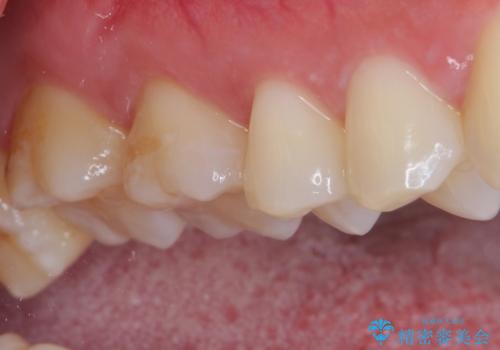

- 銀歯をセラミックにしたいとのことで来院された患者様です。